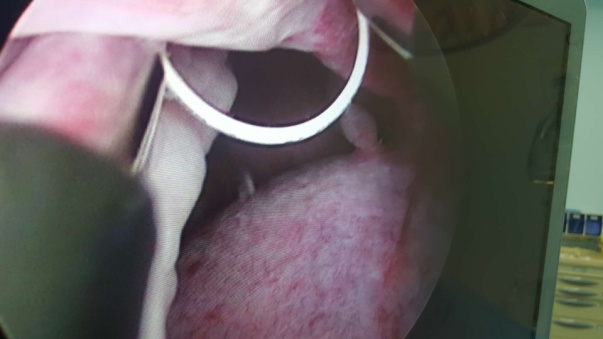

在孙伍柒主任支持、指导下,泌尿外科专家团队制定了详细的手术治疗方案,由雷永刚副主任医师以及李永炜医生成功为患者进行了硬膜外麻醉阴囊镜下左侧睾丸鞘膜切除术,手术切口只有1cm,术中发现睾丸还有一附件,睾丸附件易扭转并导致疼痛等急症,为防止以后附件扭转予以镜下一并切除。术后第3天患者康复出院。出院时患者非常满意。

据介绍,传统的阴囊内手术是在阴囊壁做一个5-12cm的长切口,然后再将病灶切除、缝合切口,该手术切口长、创伤大,易继发伤口感染,恢复慢,住院时间长。而阴囊镜微创手术只须在阴囊皮肤上做一个0.5-1.0cm长切口,整个手术过程直观、精细,创伤小,恢复快,伤口小,术后仅需缝合0-1针,住院约3-5天。